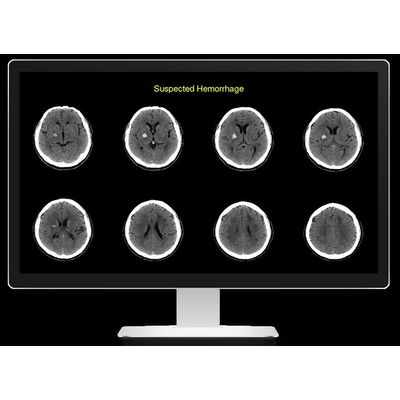

Rapid - Version ICH -Identifies Suspected Intracranial Hemorrhage Software

Rapid ICH uses the latest artificial intelligence technology to quickly triage non-contrast CT (NCCT) cases and notify clinicians of possible intracranial hemorrhage (ICH). It helps stroke and trauma team members on the front lines of patient assessment streamline decision-making and expedite patient care.

Rapid ICH automatically processes images and assesses them for hemorrhage, including intraparenchymal (IPH), intraventricular (IVH), subdural (SDH), and subarachnoid (SAH) subtypes—presenting clear, easy-to-read results that make it easier for physicians to make critical decisions faster.

- Fast. Rapid ICH identifies the suspicion of suspected intracranial hemorrhage and sends results to trauma and stroke team members in 3 minutes or less.

- Accurate. Leveraging intelligence gained from more than a thousand scans analyzed from hospitals and clinics around the world, Rapid ICH identifies all types of suspected hemorrhage, including IPH, IVH, SDH and SAH, with a sensitivity of 95% and specificity of 94%, excluding hemorrhagic transformations (HTs).